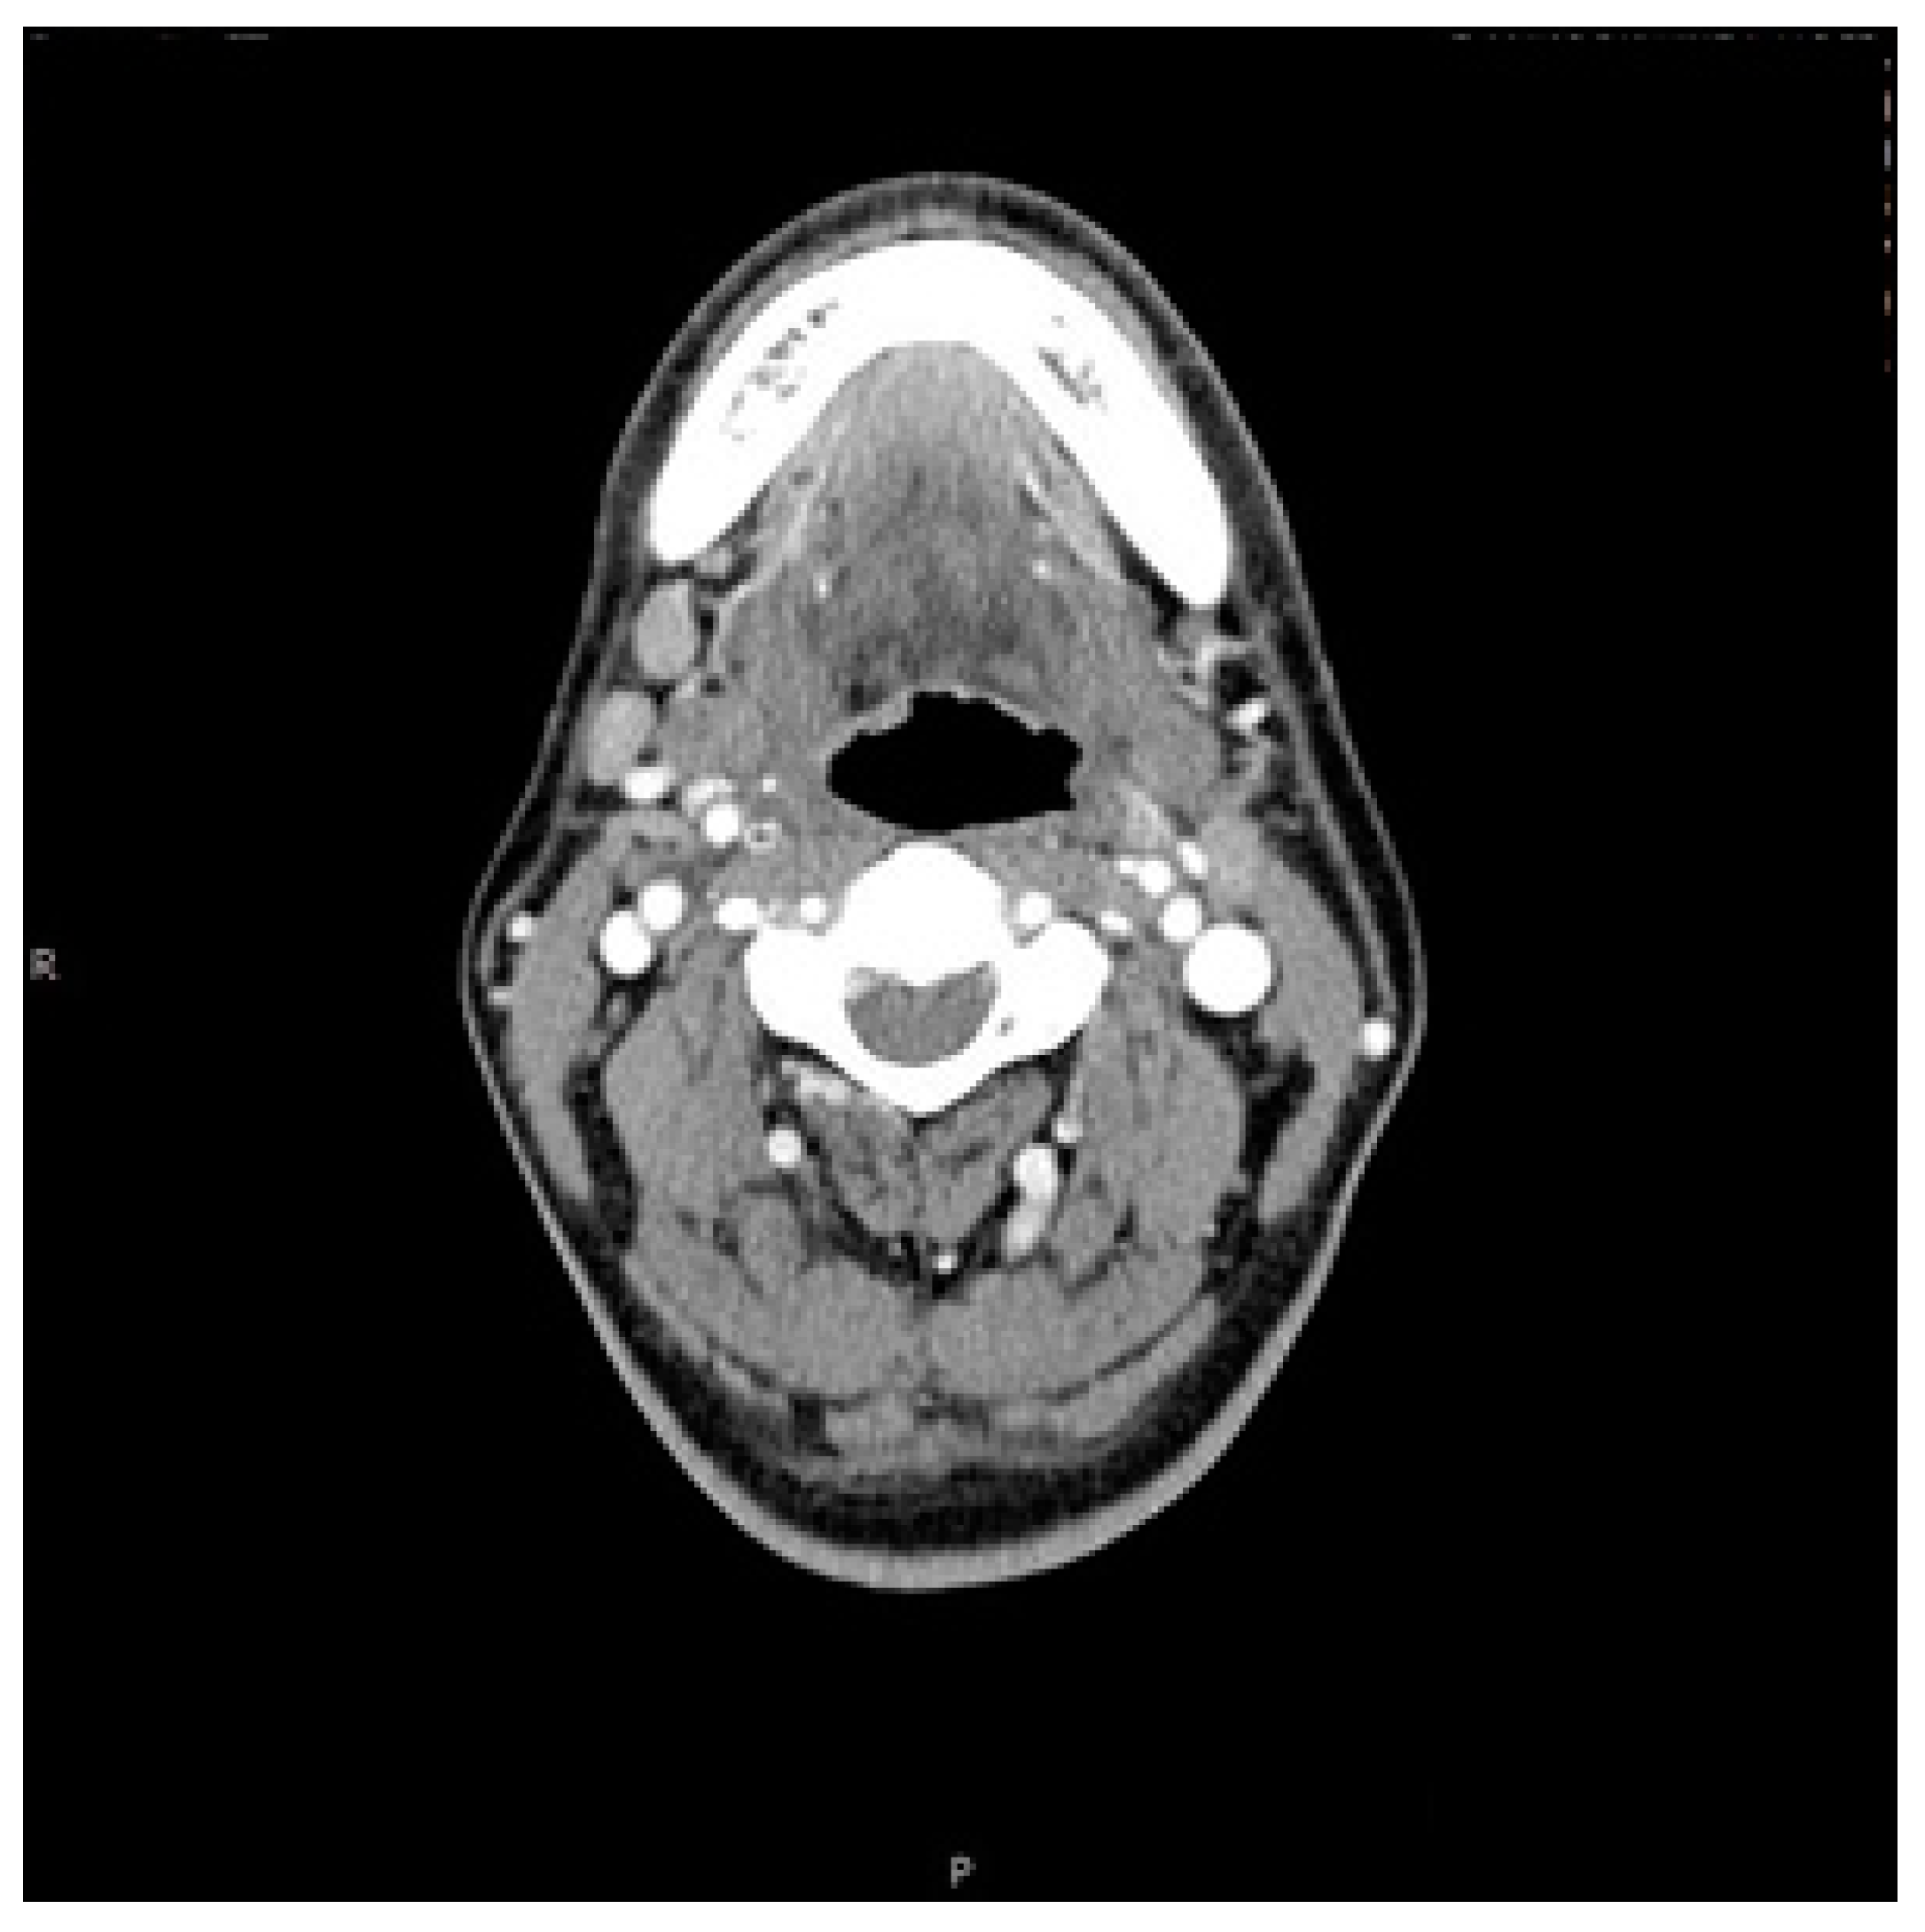

2. Case Report